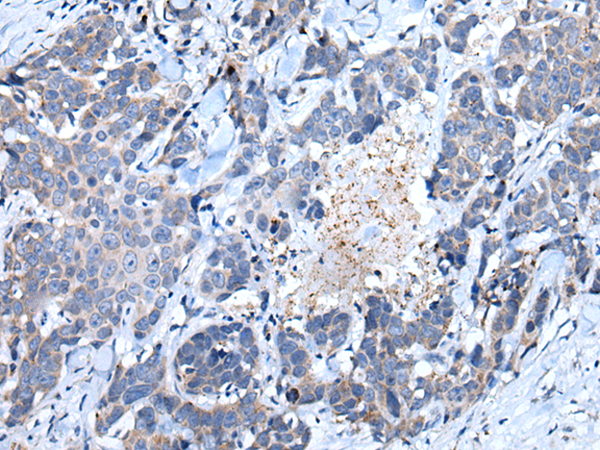

分类: 科研抗体货号: P10813别名: SAG; GP340; SALSA; muclin应用: IHC反应种属: Human, Mouse, Rat